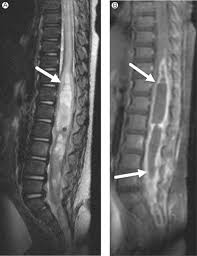

Central Canal Of Spinal Cord : 31 Prominent Central Canal Radiology Key / The space almost acts as a the human central canal of the spinal cord:. Curiously, with the spinal cord alone, many autonomic functions and even voluntary movements can occur. The central canal spans the length of the spinal cord from the caudal angle of the fourth ventricle to the conus medullaris. Clinical signs of spinal cord infarction include muscle weakness and paralysis with loss of reflexes. The central channel ( central canal ) is situated in the center of the spinal cord canal which contains cerebrospinal fluid. Spinal cord injury — spinal cord injuries classification and external resources view of the vertebral column and spinal cord icd 10 g …

The central canal is continuous with the ventricular system of the brain. As part of the central nervous system, the spinal cord (medulla spinalis) is held in place by ligaments and is well protected in the spinal canal of the vertebral column. It starts at the foramen magnum as the. Clinical signs of spinal cord infarction include muscle weakness and paralysis with loss of reflexes. Spinal cord histology (transverse section): Gray matter (derived from embryonic mantle layer) is. Farlex partner medical dictionary © farlex 2012. Spinal canal and spinal cord.

Clinical signs of spinal cord infarction include muscle weakness and paralysis with loss of reflexes.

Together with the cerebral ventricles, and the subarachnoid space of the central channel forms a single common cavity, since all. Haverkamp peter winningham winnie c. The central canal lies below and is connected to the ventricular system of the brain, from which it receives cerebrospinal fluid, and shares the same ependymal lining. The core consists mainly of two posterior (dorsal) horns, which extend toward the posterolateral surfaces of the cord, and two thicker anterior (ventral) horns, which extend toward the. Spinal cord cross section central canal. Surrounding the spinal cord and projecting downward is a slim connecting filament where the spinal cord ends (filum terminale). Gray matter (derived from embryonic mantle layer) is. Many present with serious acute symptoms such as paresthesia, paralysis, and loss of sensation or bladder and bowel function. The spinal cord forms a nearly cylindrical column that is situated within the spinal canal of the vertebral column. The central canal spans the length of the spinal cord from the caudal angle of the fourth ventricle to the conus medullaris. Spinal cord infarction (also known as a spinal stroke) refers to the death of nervous tissue, which results from an interruption of the arterial supply. The most common causes of infarction are vertebral. Central nervous system spinal cord.